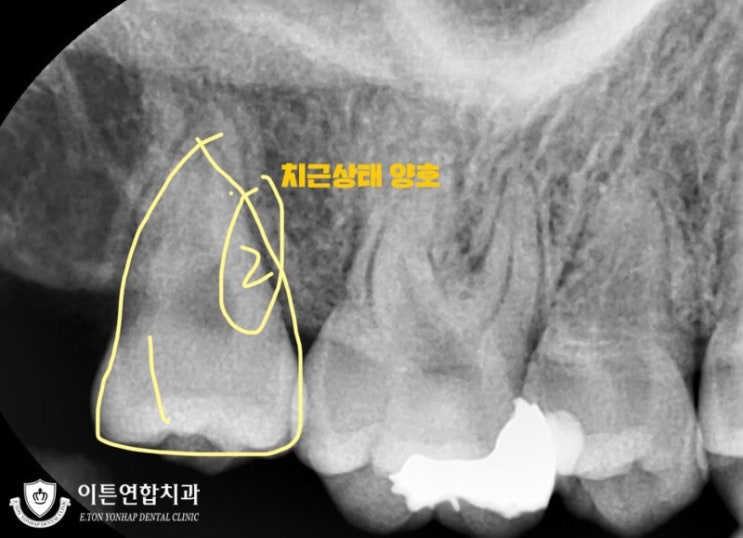

같은 자리에 사랑니가 두 개 난,, 쌍사랑니 발치 후기(선천치+과잉치 대환장 콜라보)

안녕하세요 오늘은 사랑니 발치 후기를 가져왔어요 원래 쓸 생각은 없었는데요 다 뽑고 나니 쌍사랑니라고 ...